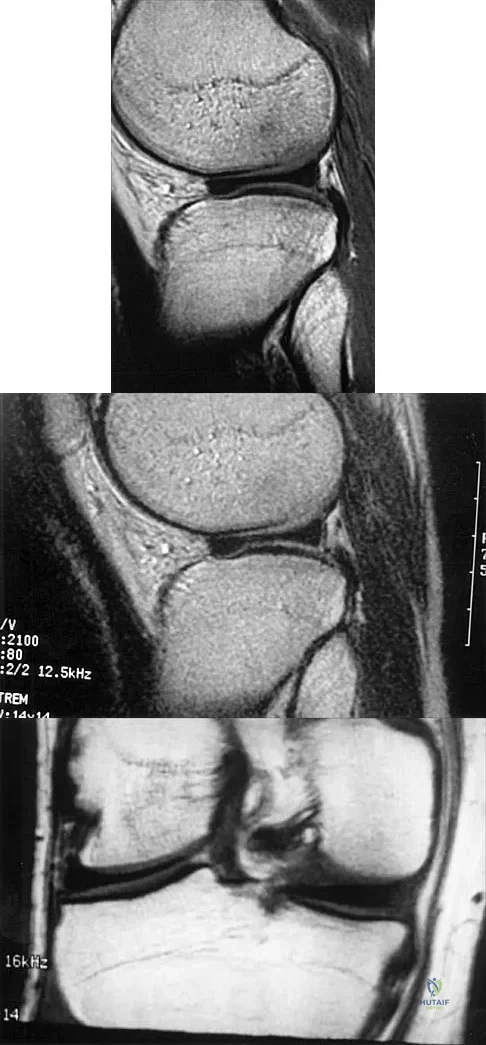

A 73-year-old woman reports a 4-month history of severe left-sided posterior buttock pain and left leg pain. The leg pain radiates into the left lateral thigh and posterior calf with cramping. Examination reveals mild difficulty with a single-leg toe raise on the left side and a diminished ankle reflex. There is also a significant straight leg raise test at 45 degrees which exacerbates symptoms. An MRI scan is shown in Figure 4. What is the most appropriate treatment at this time?

Explanation

Lumbar spinal stenosis with lumbar radiculopathy can be commonly caused by a synovial cyst arising from the facet joints. Lyons and associates reported on the surgical treatment of synovial cysts in 194 patients. Of the 147 with follow-up data, 91% reported good pain relief and 82% had improvement of their motor deficits. Epstein reported a 58% to 63% incidence of good/excellent results and a 38 to 42 point improvement on the SF-36 Physical Function Scale. It was also suggested that since the presence of a synovial cyst indicates facet pathology, possible fusion should be considered in these patients, especially those with underlying spondylolisthesis. Lyons MK, Atkinson JL, Wharen RE, et al: Surgical evaluation and management of lumbar synovial cysts: The Mayo Clinic Experience. J Neurosurg 2000;93:53-57. Khan AM, Synnot K, Cammisa FP, et al: Lumbar synovial cysts of the spine: An evaluation of surgical outcome. J Spinal Disord Tech 2005;18:127-131.